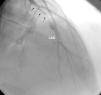

ResultsEleven patients who presented with ACS and were diagnosed with MPNs were studied (nine men, two women, mean age 40.18±8.4 years). Six patients had no major CV risk factors; only one had two risk factors, while the rest had one. The patients’ mean age was 32.9±6 years when they first suffered MI. Case 1 also had concomitant jugular vein thrombosis, case 2 had portal vein thrombosis and case 11 had peripheral arterial thrombosis. Splenomegaly was seen in five patients and hepatosplenomegaly in two. Ten patients had anterior MI and one had inferior MI. In two patients (cases 2 and 4) MI was complicated by cardiac arrest. On coronary angiography, six patients had left anterior descending (LAD) lesions (Figure 1 and Supplementary Video 1 represent case 4), two patients had LAD and concomitant diagonal lesions, one patient had LAD and circumflex artery lesions, one patient had a right coronary artery lesion and one patient's angiography was normal. All lesions were thrombotic, causing total or sub-total occlusion, and coronary arteries other than the infarct-related arteries were normal. Nine patients underwent percutaneous coronary intervention and two patients underwent coronary artery bypass grafting due to dissection of the LAD (Table 1).

Data on which coronary arteries are most affected in ACS related to MPNs are scarce; in our study LAD lesions and anterior MI were predominant.